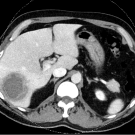

Fatema Dabdoub, MD; Haneen AbdelKhaleq, DO; Victoria Udezi, MD; Zaiba Jetpuri, DO; Nora Gimpel, MD

A 56-year-old man presented to the emergency department of a large academic hospital in Dallas, TX with sudden onset abdominal pain the night prior to presentation.